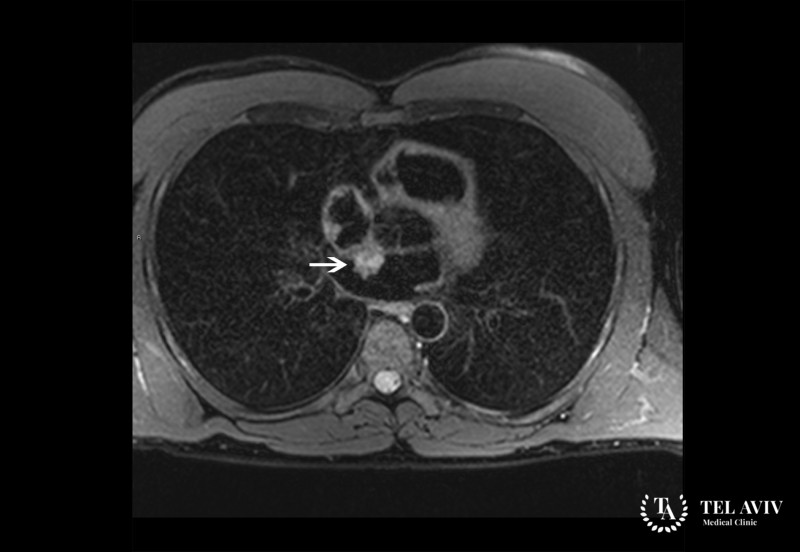

Обследуя пациента с подозрением на онкологическую патологию, специалисты ведущей в Израиле клиники применяют современные, высокоинформативные методы диагностики направленные не только на выявление очага раковой опухоли, но и метастатических поражений. С помощью передового оборудования, экспертных знаний, использования лабораторных и инструментальных способов исследования нам удается обнаружить все злокачественные участки, определить размер и вид опухоли, стадию заболевания. Опытные врачи высшей категории на основании результатов диагностики разработают индивидуальный, оптимальный протокол лечения, направленный на устранение симптомов, удаление опухоли и злокачественных клеток.